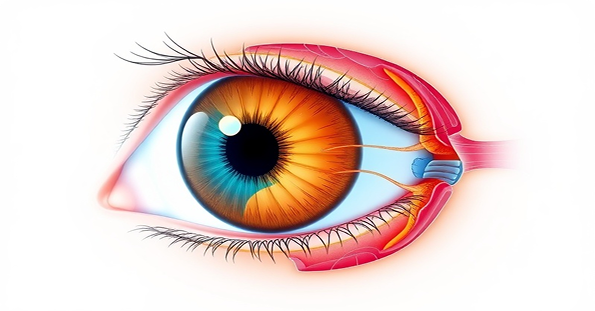

Understanding Eye

Injuries

Eye injuries can result in significant pain and vision loss, impacting every aspect of daily life. Our experienced team helps victims understand their treatment options and legal rights for compensation.

Comprehensive Care

Access to top Expert guidance through medical treatment and legal processes ardiac specialists.

Protected Rights

Ensuring fair compensation for your suffering and recovery